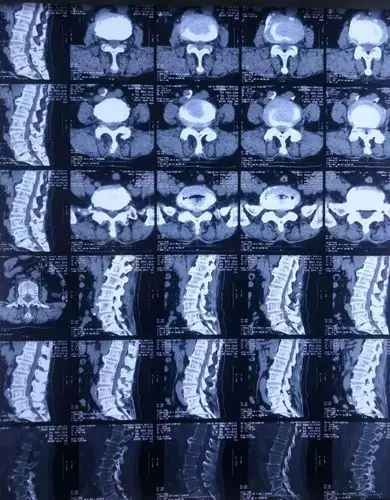

乌海市人民医院骨科刘涛主任医师独立完成腰椎间盘突出症合并腰椎滑脱